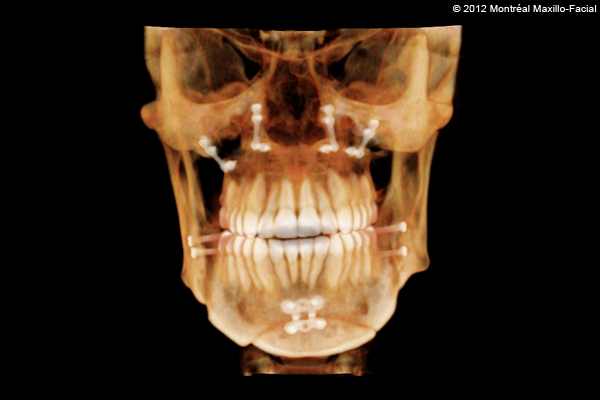

- 13 FÉVRIER 2012 - Rendez-vous avec mon chirurgien pour mes mâchoires